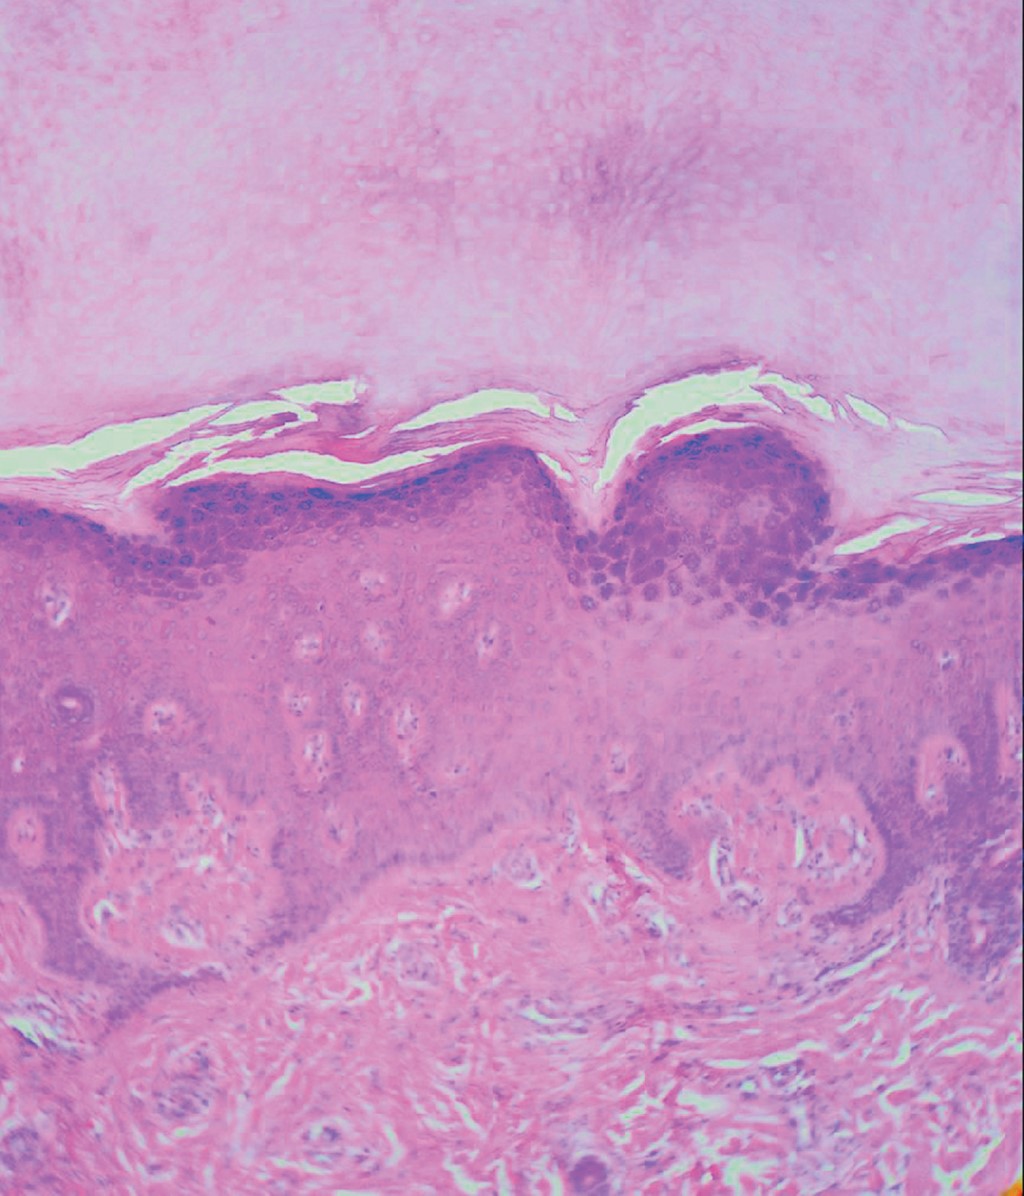

Hereditary palmoplantar keratoderma Wachters type. Communication of a case

Palmoplantar keratodermas are a heterogeneous group of diseases, characterized by marked thickening of the epidermis on the palms and soles. They may have an acquired or hereditary origin, and according to their distribution they can be, diffused, localized (nummular/ linear) or papular. In this article we present the case of a patient with Wachters' palmoplantar keratoderma, with a probable autosomic recessive inheritance, that presented keratotic localized painful plaques on palms and feet, without association to another disease.

Figure 1